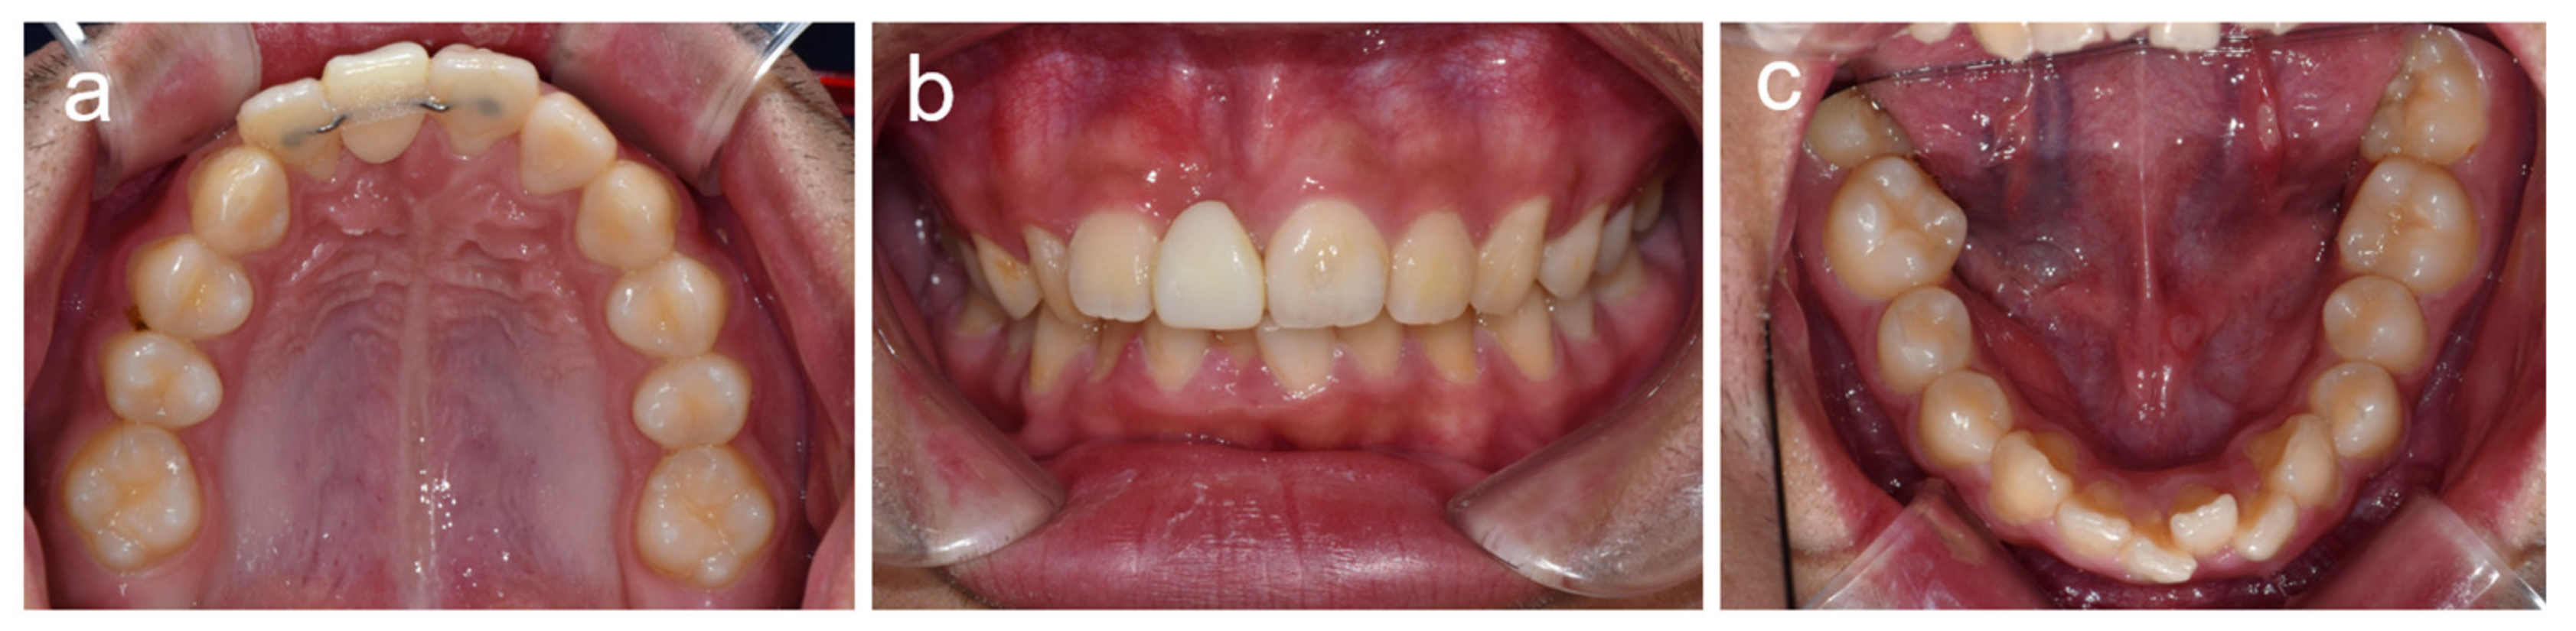

2.1. Case 1

2.2. Case 2

2.3. Case 3

2.4. Case 4

2.5. Case 5